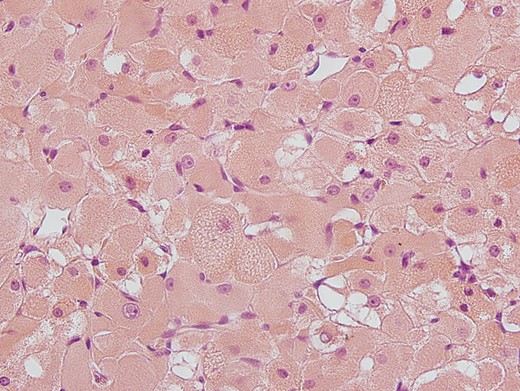

A 65-year-old male was referred to our department with a constant urge to clear the throat for a time span of 12 months. In addition, the patient stated his progressing inability to swallow food. Due to these symptoms, a resection of the thyroid gland had been carried out earlier showing struma colloides nodosae as well as bilateral parathyroidal adult rhabdomyomae. Even so, there was no relief in symptoms. At outpatient presentation at his dentist, a slight swelling of the soft palate was felt and the patient was referred for further therapy. Endoscopic examination as well as magnetic resonance imaging (MRI; Fig. 1) unveiled a tumor on the right side of the soft palate with a size of 5 × 5 cm2 and distinct demarcation to the surrounding tissue. Subsequently, the lesion was completely excised (Fig. 2) and histopathological analysis was conducted that showed a circumscribed but not encapsulated mesenchymal tumor with polygonal cell formation. The cells presented a granular cross-striated eosinophilic cytoplasm, large round vesicular nuclei and so called spiderweb cells (Fig. 3). Immunohistochemically, the cytoplasm of the cells was 100% positive for antibodies to desmin and S100 (Fig. 4). Additional immunohistochemical markers showed slight nuclear positivity for myogenin and nuclear negativity for AE1/3, CD68 as well as melan A. The histological examination confirmed ARM without signs of malignancy. At a total follow-up of 3 years, including MRI scan, no signs of recurrence were detected.

Immunohistological staining of EARM with desmin antibodies. Cytoplasma with positive antibodies for desmin is seen.